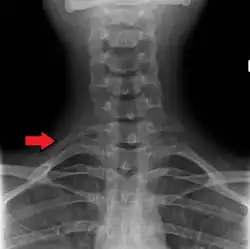

Variations in the number of ribs occur. About 1 in 200–500 people have an additional cervical rib, and there is a female predominance.[13] Intrathoracic supernumerary ribs are extremely rare.[14] The rib remnant of the 7th cervical vertebra on one or both sides is occasionally replaced by a free extra rib called a cervical rib, which can mechanically interfere with the nerves (brachial plexus) going to the arm.

The number of ribs as 24 (12 pairs) was noted by the Flemish anatomist Vesalius in his key work of anatomy De humani corporis fabrica in 1543, setting off a wave of controversy, as it was traditionally assumed from the Biblical story of Adam and Eve that men's ribs would number one fewer than women's.[20][21] However, thirteenth or "cervical ribs" occur in 1% of humans[12] and this is more common in females than in males.[13]